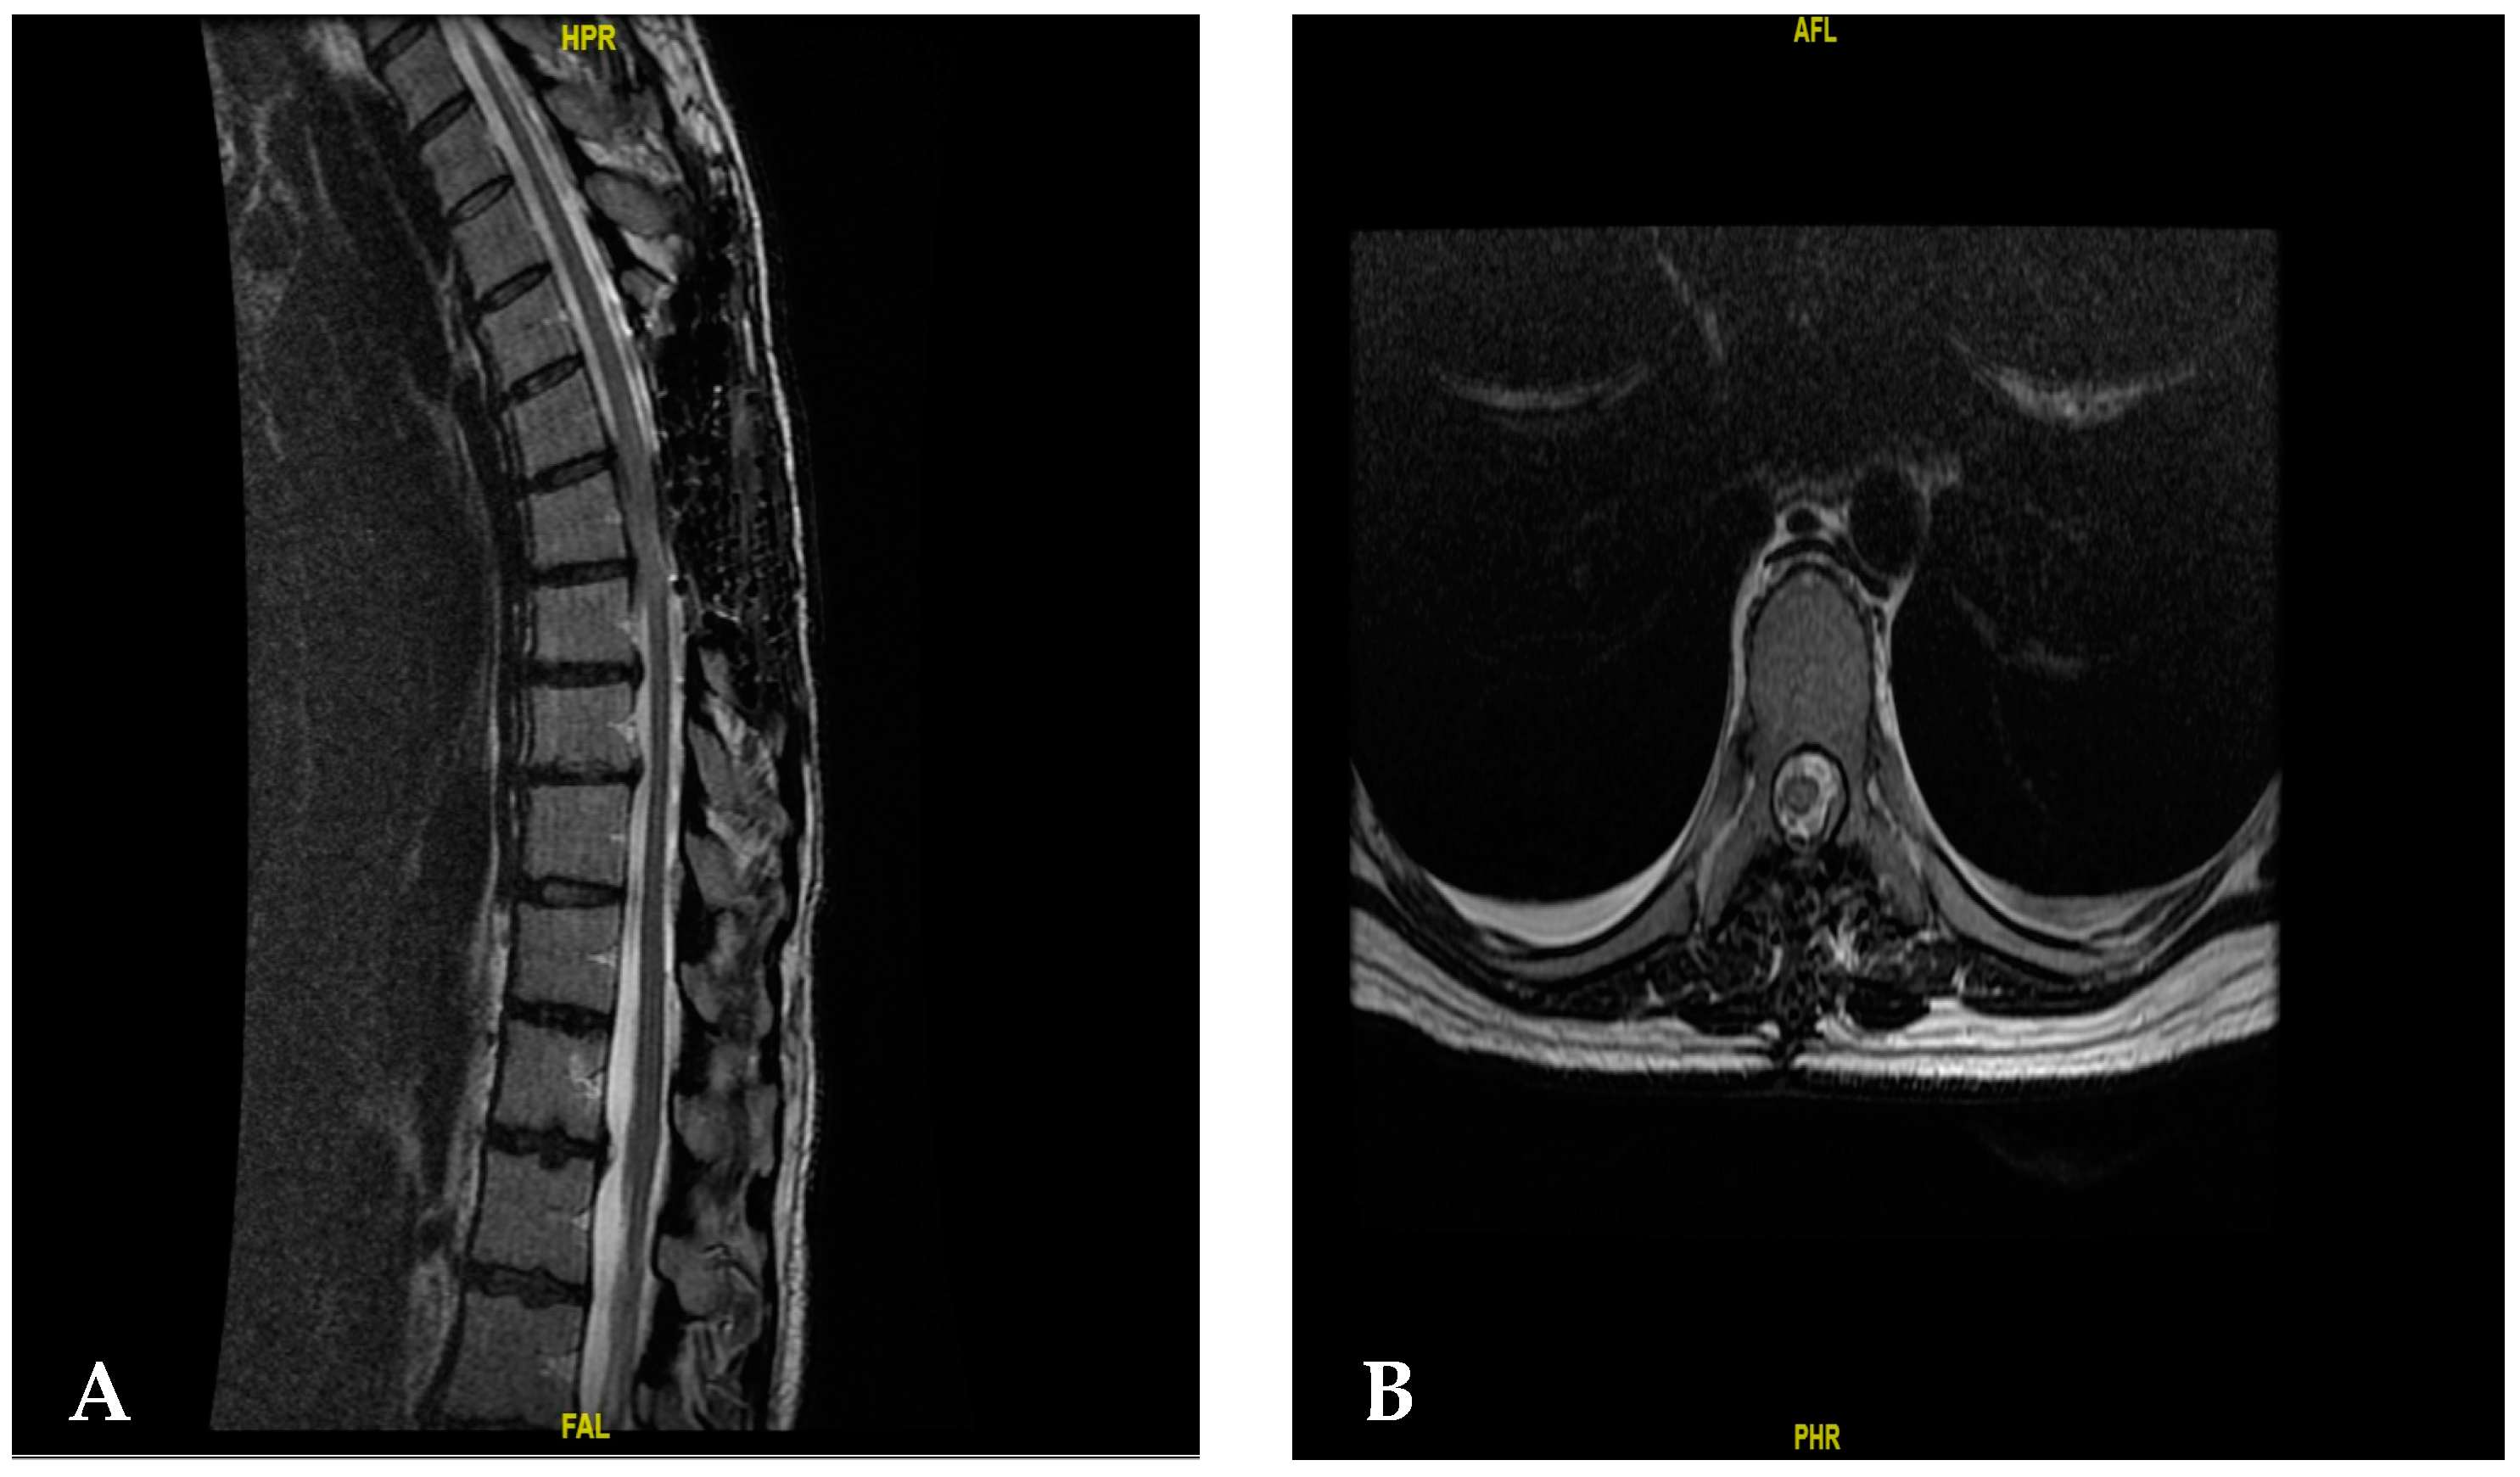

Therefore, a new resection was performed one week later. In this procedure, the cephalic and rostral parts were monitored to observe the limits, laminectomy was completed, and it was possible to see healthy dura mater. The resection was completed, and we observed nerve exit holes and resected the lesion in its entirety (Figure 3).

Figure 3.

(A) Post-operative image after the second surgical intervention, showing complete tumor resection with a hyperintense image showing hemostatic material. (B) Axial post-operative image after the second surgery.

After one year of follow-up, the patient has improved favorably since she has a muscle strength of 5/5 on the Daniel’s scale, as well as urinary function and sensitivity, which allows her to walk freely (Figure 4).

Figure 4.

(A) An image showing the follow-up of the patient 6 months after the first surgery in the sagittal section. (B) Am image showing the follow-up of the patient 6 months after the second surgery in the axial section.